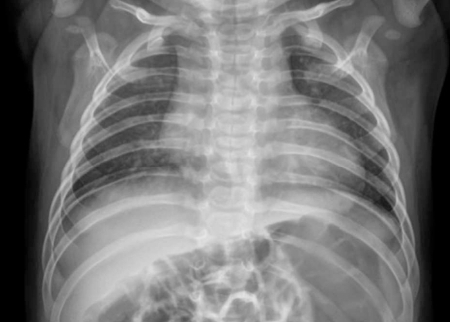

감염된 영아는 발열, 기침, 가래, 콧물 등의 호흡기 증상과 함께 급성 중이염과 간 기능 이상을 보였고 폐렴이 동반됐다. 특히 간 기능 수치(AST/ALT)가 462/350 IU/L로 비정상적으로 높았다. 코로나19는 주로 폐렴을 유발하지만, 이 바이러스는 폐렴뿐만 아니라 간 기능 이상도 동반했다는 점이 특징으로 지목된다. 다행히 영아는 치료를 통해 간 기능과 호흡기 증상이 호전돼 8일 만에 퇴원했다. 연구팀은 "사람 간 전파 가능성은 추가 연구가 필요하다"고 밝혔다.